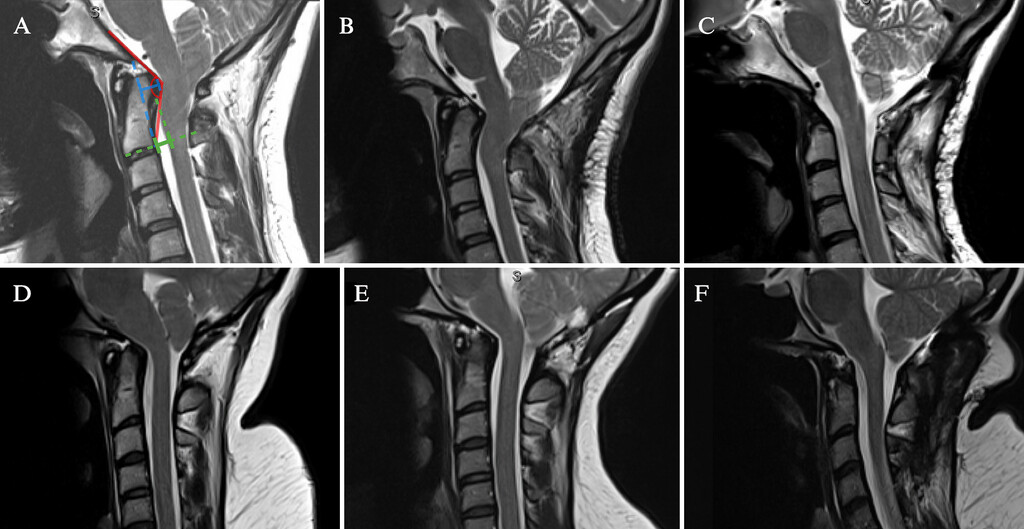

🧠 DISECCIÓN CAROTÍDEA 2026

1️⃣ Principal causa de stroke en menores de 50 años

2️⃣ Tríada clave: dolor cervical/facial + Horner + déficit neurológico